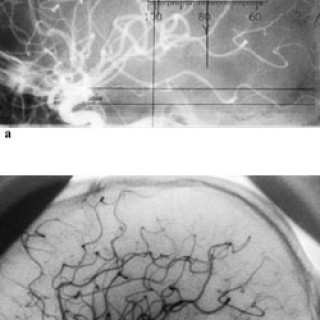

Pasientar med akutt innsetjande brystsmerter er ei stor diagnostisk utfordring. Symptomet kan oftast tilskrivast kardiovaskulære, pulmonale, muskel- og skjelettopphavelege eller psykiske lidingar, men tilstandar i gastrointestinalkanalen kan o†g gje opphav til dette symptomet. Spontan oesophagusruptur, også kalla Boerhaaves syndrom, er ei høgst uvanleg årsak til akutte brystsmerter. Pasienten . Mann, fødd i 1912, budde heime og hadde tidlegare stort sett vore frisk, men fekk i 2000 innlagt permanent kateter pga. urinretensjon. Ein dag i april 2001 då han skulle ete middag, fekk han akutt...